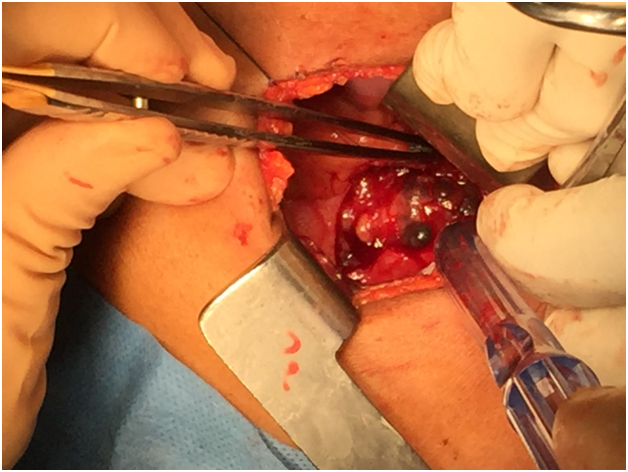

The patient was taken to the operating room where, via a limited right infra-mammary incision and under general anesthesia, pericardial window (Figure 1C) biopsies of the adherent pericardium, the mass invading the right ventricle, and a pulmonary wedge resection of nodules in the right lower lobe were made.

Figure 1C Intraoperative photo showing pericardial window.

Intraoperatively and grossly, the tumor was noted to be markedly firm and dark red in color. Frozen section of tissue from a lung nodule in the right lower lobe showed a high-grade malignant neoplasm with large pleomorphic cells and frequent mitoses.